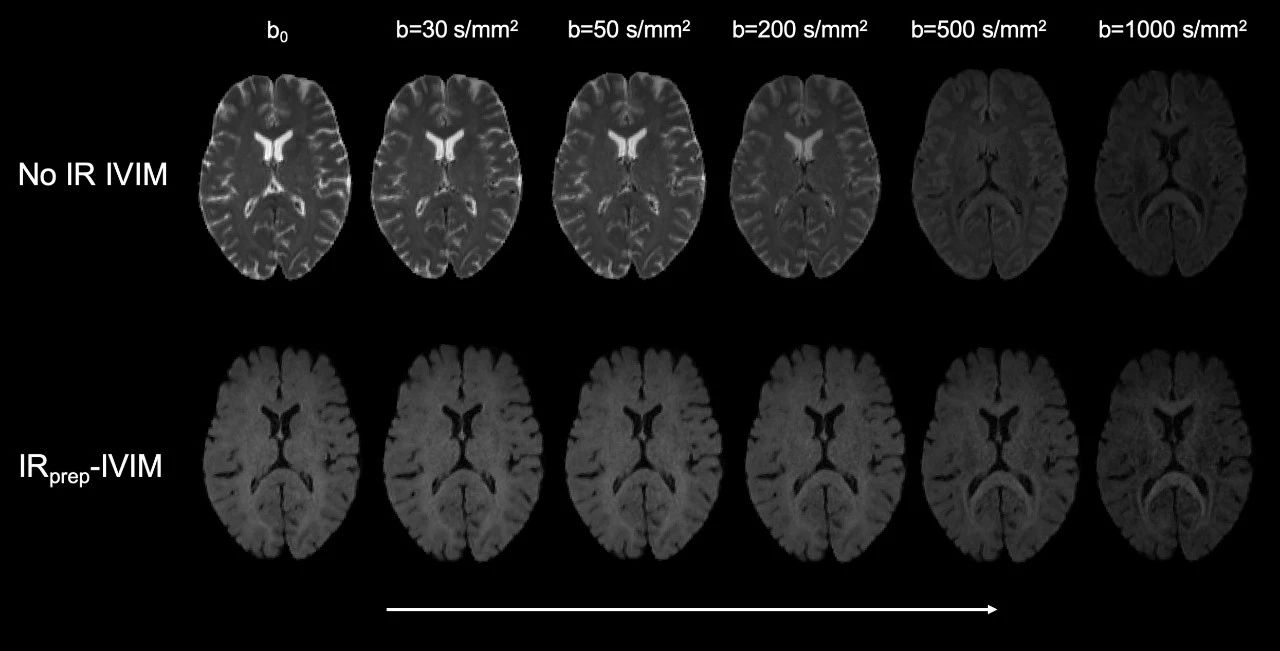

《通过反转恢复准备的IVIM MRI推进脉络丛微血管灌注估计》

Advancing Estimation of Microvascular Perfusion in the Choroid Plexus through Inversion Recovery Prepared IVIM MRI

本研究的目的是通过使用反转恢复准备的IVIM MRI技术,改进对脉络丛(CP)微血管灌注的估计。研究者使用了高分辨率的IVIM MRI技术,结合反转恢复准备,对脉络丛的微血管灌注进行了分析。结果表明,使用反转恢复准备的IVIM MRI技术可以显著提高脉络丛微血管灌注的估计准确性。讨论部分强调了该技术在区分脉络丛和脑脊液信号方面的潜力,并可能为脉络丛的血流动力学提供新的见解。结论指出,该研究提供了一种新的技术方法来探索脉络丛的血管灌注,可能对理解脉络丛在脑脊液生产和循环中的作用具有重要意义。

c55c6c6a78d000c943cc0d50995dd1b3.jpg

使用传统IVIM和IRprep-IVIM 捕获的代表性图像,b值为0、30、50、200、500和1000s/mm2。带或不带反转恢复模块的非扩散加权b0图像突显了通过反转恢复应用成功抑制CSF信号。